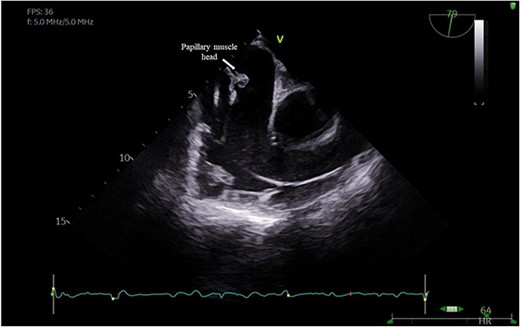

He had a redo-median sternotomy. Cardiopulmonary bypass was instituted through aortic cannulation connected to the bypass machine via a bifurcated arterial line along with the femoral ECMO cannula. The SVC and IVC were cannulated before opening the right atrium. The TV was inspected which revealed a flail anterior leaflet, attached to the ruptured head of the papillary muscle (Fig. 3).

Intraoperative pictures demonstrating a flail anterior leaflet attached to the ruptured head of the papillary muscle.